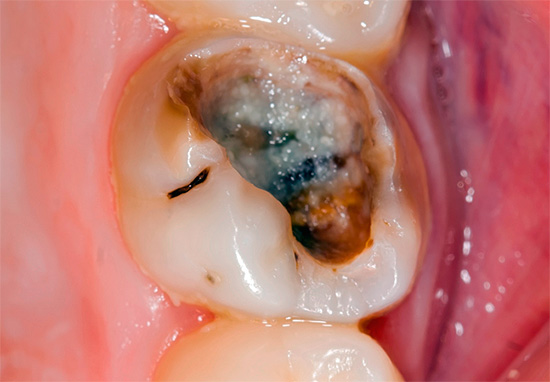

A foto mostra como um dente permanente se parece em um adulto vários anos após o tratamento da pulpite com o uso da mistura de resorcinol-formalina: